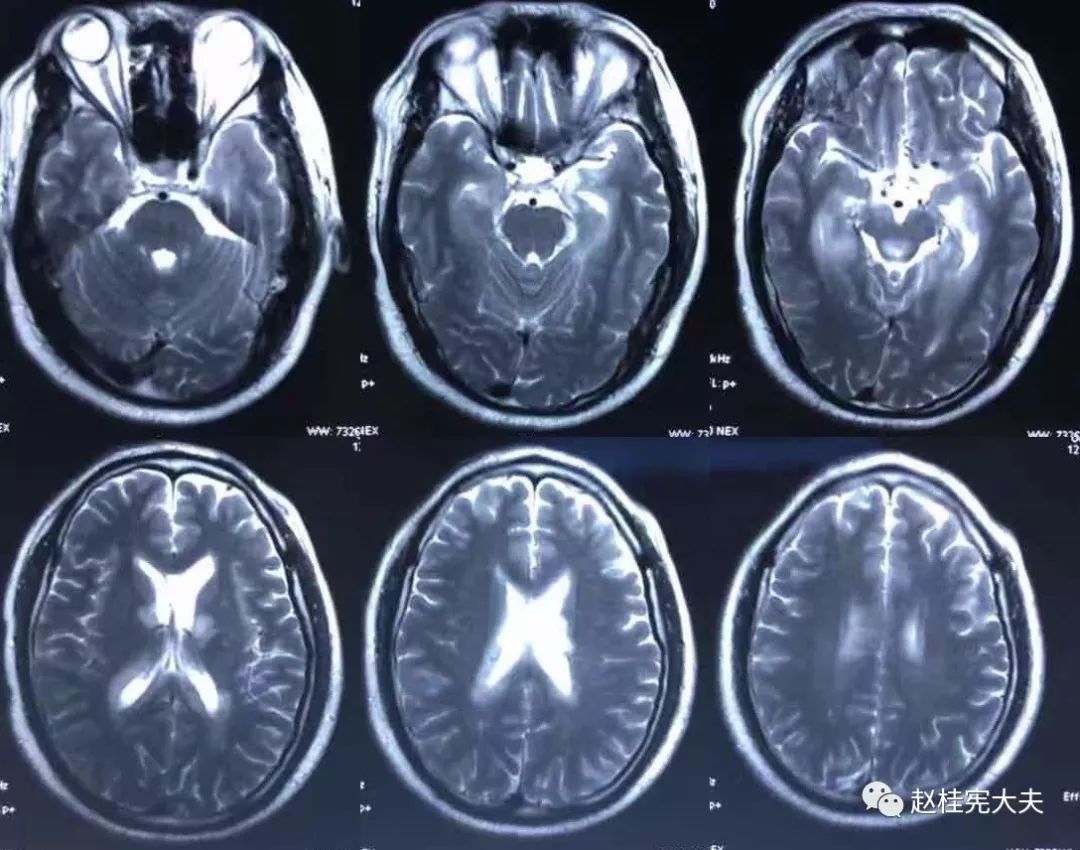

2018.7.6头颅MRI:胼胝体、穹隆及双侧脑室旁、基底节区、右侧延髓、桥臂异常信号,脱髓鞘病变考虑。头颅MRS:左枕叶病变区MRS显示:NAA下降,Cho升高,Cho/NAA=3.86,并见倒置乳酸峰。

2018.7.10磁共振增强:脑室周边病灶轻度强化。

7.20复查头颅MRI平扫:胼胝体、穹隆及双侧脑室旁、基底节区、右侧延髓、桥臂广泛信号异常,对照前片(7.10)范围明显缩小。

2018.10复查头颅MRI:胼胝体压部、左侧部分枕颞叶、侧脑室枕角旁、中脑脱髓鞘病变,视神经脊髓炎谱系病?结合对照前片(7.4)病变范围有所缩小。

我看到患者时的思考:当了解了患者前期诊疗经过后,在看到患者磁共振片子时,我的第一反应就是淋巴瘤。尽管患者激素治疗后症状有好转,病灶在磁共振上看起来也是有好转,但淋巴瘤也会出现这样的表现。

我对满脑室边的病灶的体会是:遇到这样的病例,首先要考虑感染、肿瘤(如室管膜瘤、生殖细胞瘤、淋巴瘤或转移瘤脑室播散等等),炎症要放到后面去考虑,脱髓鞘的诊断要打个大大大大的?。炎症中,血管炎不像,自免脑也不是很支持,尽管边缘系统似乎也有受累,但患者边缘叶脑炎的精神、行为异常、癫痫等症状很少,而且磁共振上看去除了边缘系统,整个脑室系统都有受累,这个和常见自免脑不符。视神经脊髓炎谱系病?尽管病灶在水通道蛋白富集区,但这样的视神经脊髓炎(视神经和脊髓均未受累,近脑室边的异常信号)至少罕见,即使诊断,也应该是排除其它的疾病后才可能考虑。

患者住院期间还请眼科会诊,除双眼玻璃体轻度浑浊,视力、视野、OCT均未见明显异常,未建议行玻切明确诊断。患者入院后嗜睡症状有加中,但一直未诉头痛,仅是头昏,静滴甘露醇症状减轻不明显。复查头颅磁共振平扫+增强:病灶范围较前明显扩大。轻度强化。